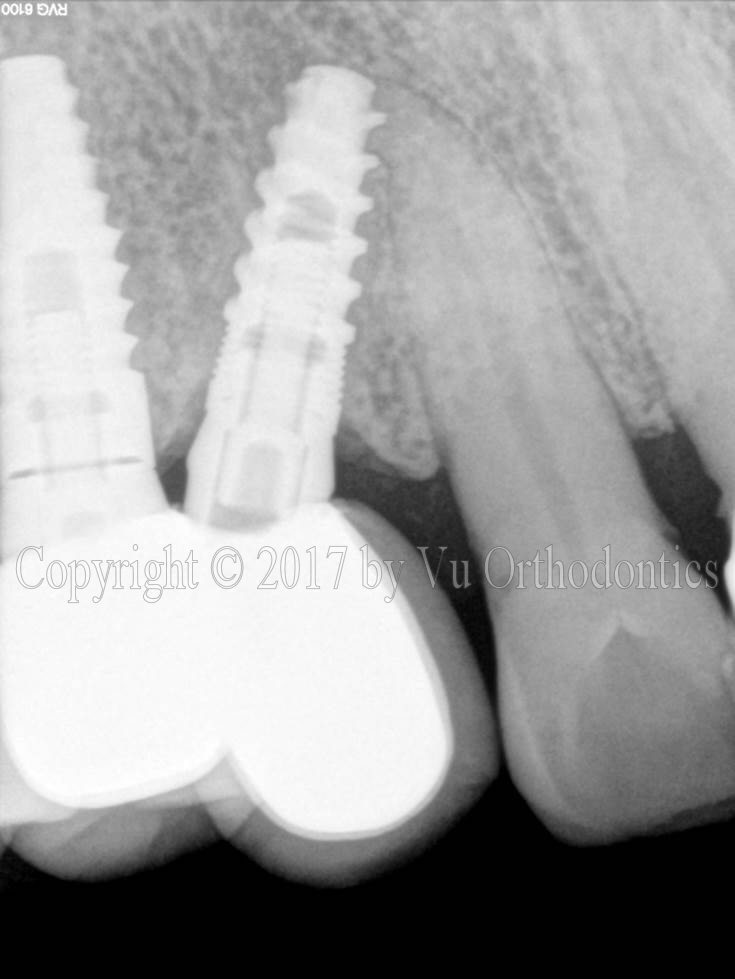

Another case of poor implant placement (which was done elsewhere) is shown in Fig. 2. In this case, the implant (in the middle) caused a damage to the adjacent natural tooth.

Fig. 2. Another poor implant placement